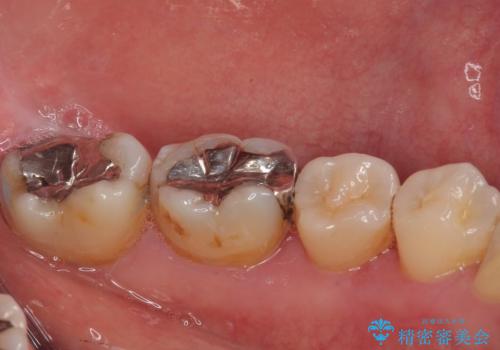

- 当院で矯正後に銀歯が目立つのでやり替えたいと来院された患者様です。銀色の詰め物(メタルインレー)と歯の間に隙間を認め、あまり歯を削りたくないとのことで、患者様と相談の結果セラミックインレーでの治療を行うことになりました。

拡大鏡視野下で、銀色の詰め物(メタルインレー)、保険のプラスチック、虫歯の除去を行い、セラミックインレーに適した形に整えました。